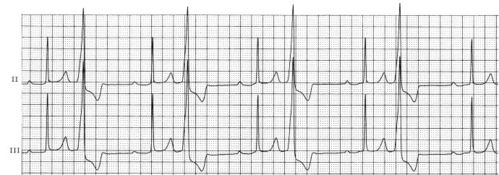

图2.14 室性早搏二联律

室性早搏二联律

室性早搏二联律心电图

室早二联律心电图